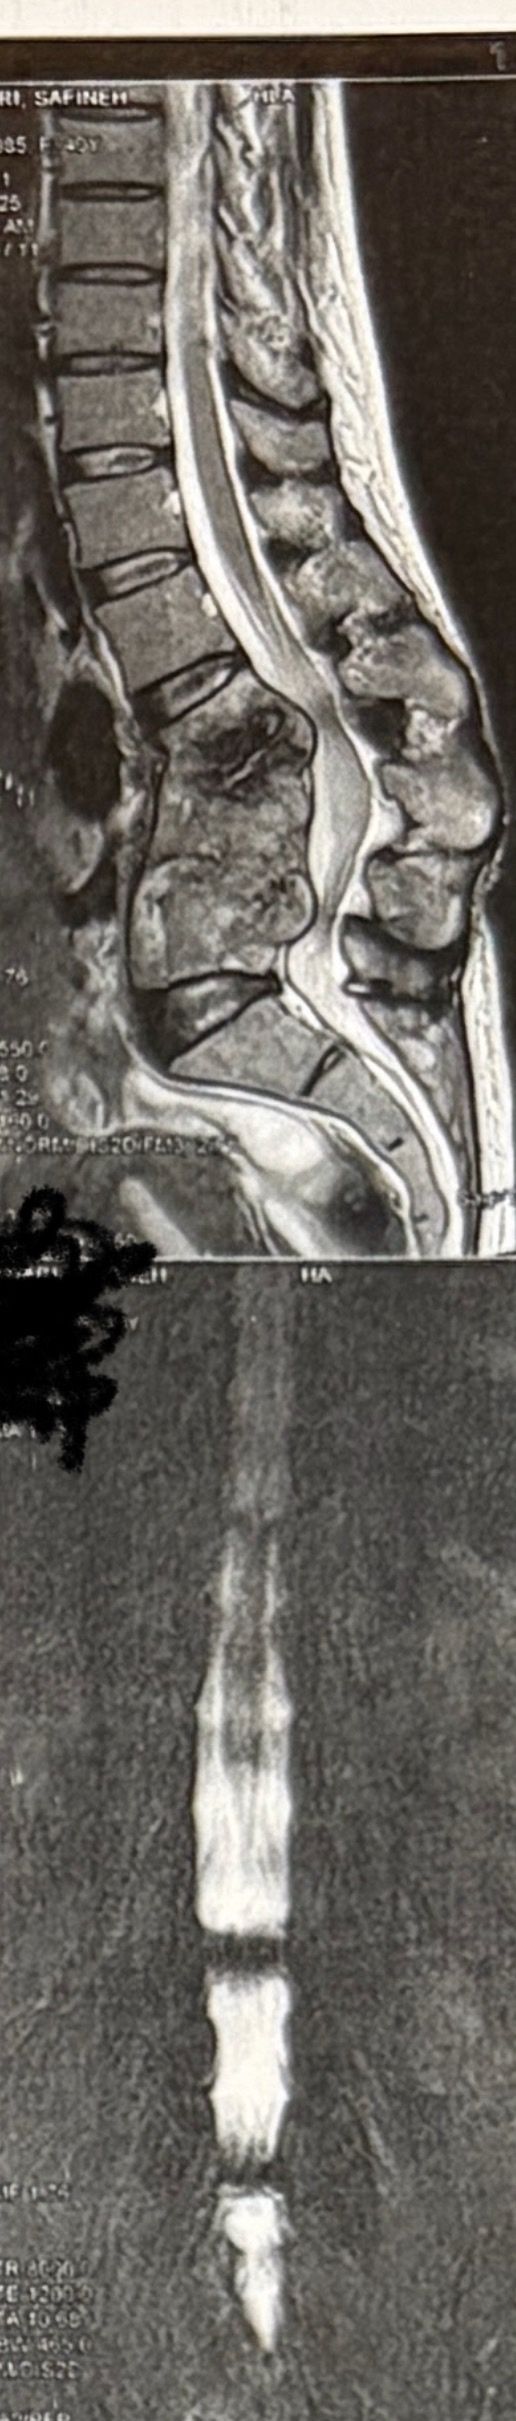

46 years old female patient presented to my clinic yesterday june 1/2025 with LBP and radicular L leg pain for several months which hasn’t responded to physio 2 neurosurgeons have visited her and didn’t suggest any surgery Neurological exam was unremarkable please see her mri/ emg/ncv and her huge tarlov cyst and possible L IVF L4-5 hyperbulge I ordered sacrum mri and ct scan and new emg/ncv and asked her with her sacral Ct scan and MRI first sees another two famous neurosurgeons and see if that large cyst is the reason for her pain if not i can work on her L4-S1 area Do you think her radicular pain can originate from her large cyst in sacrum? Do you consider surgery and removing her sacral cyst?